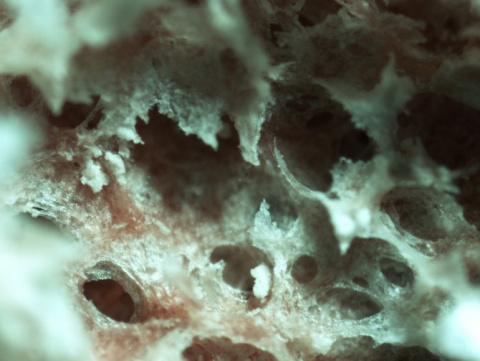

Jasmine Martínez (izquierda), Christine Liu, María Soledad Ramírez (directora del estudio), Nyah Rodman y Jennifer Fernández, en la Universidad Estatal de California en Fullerton (CSUF), de Estados Unidos.